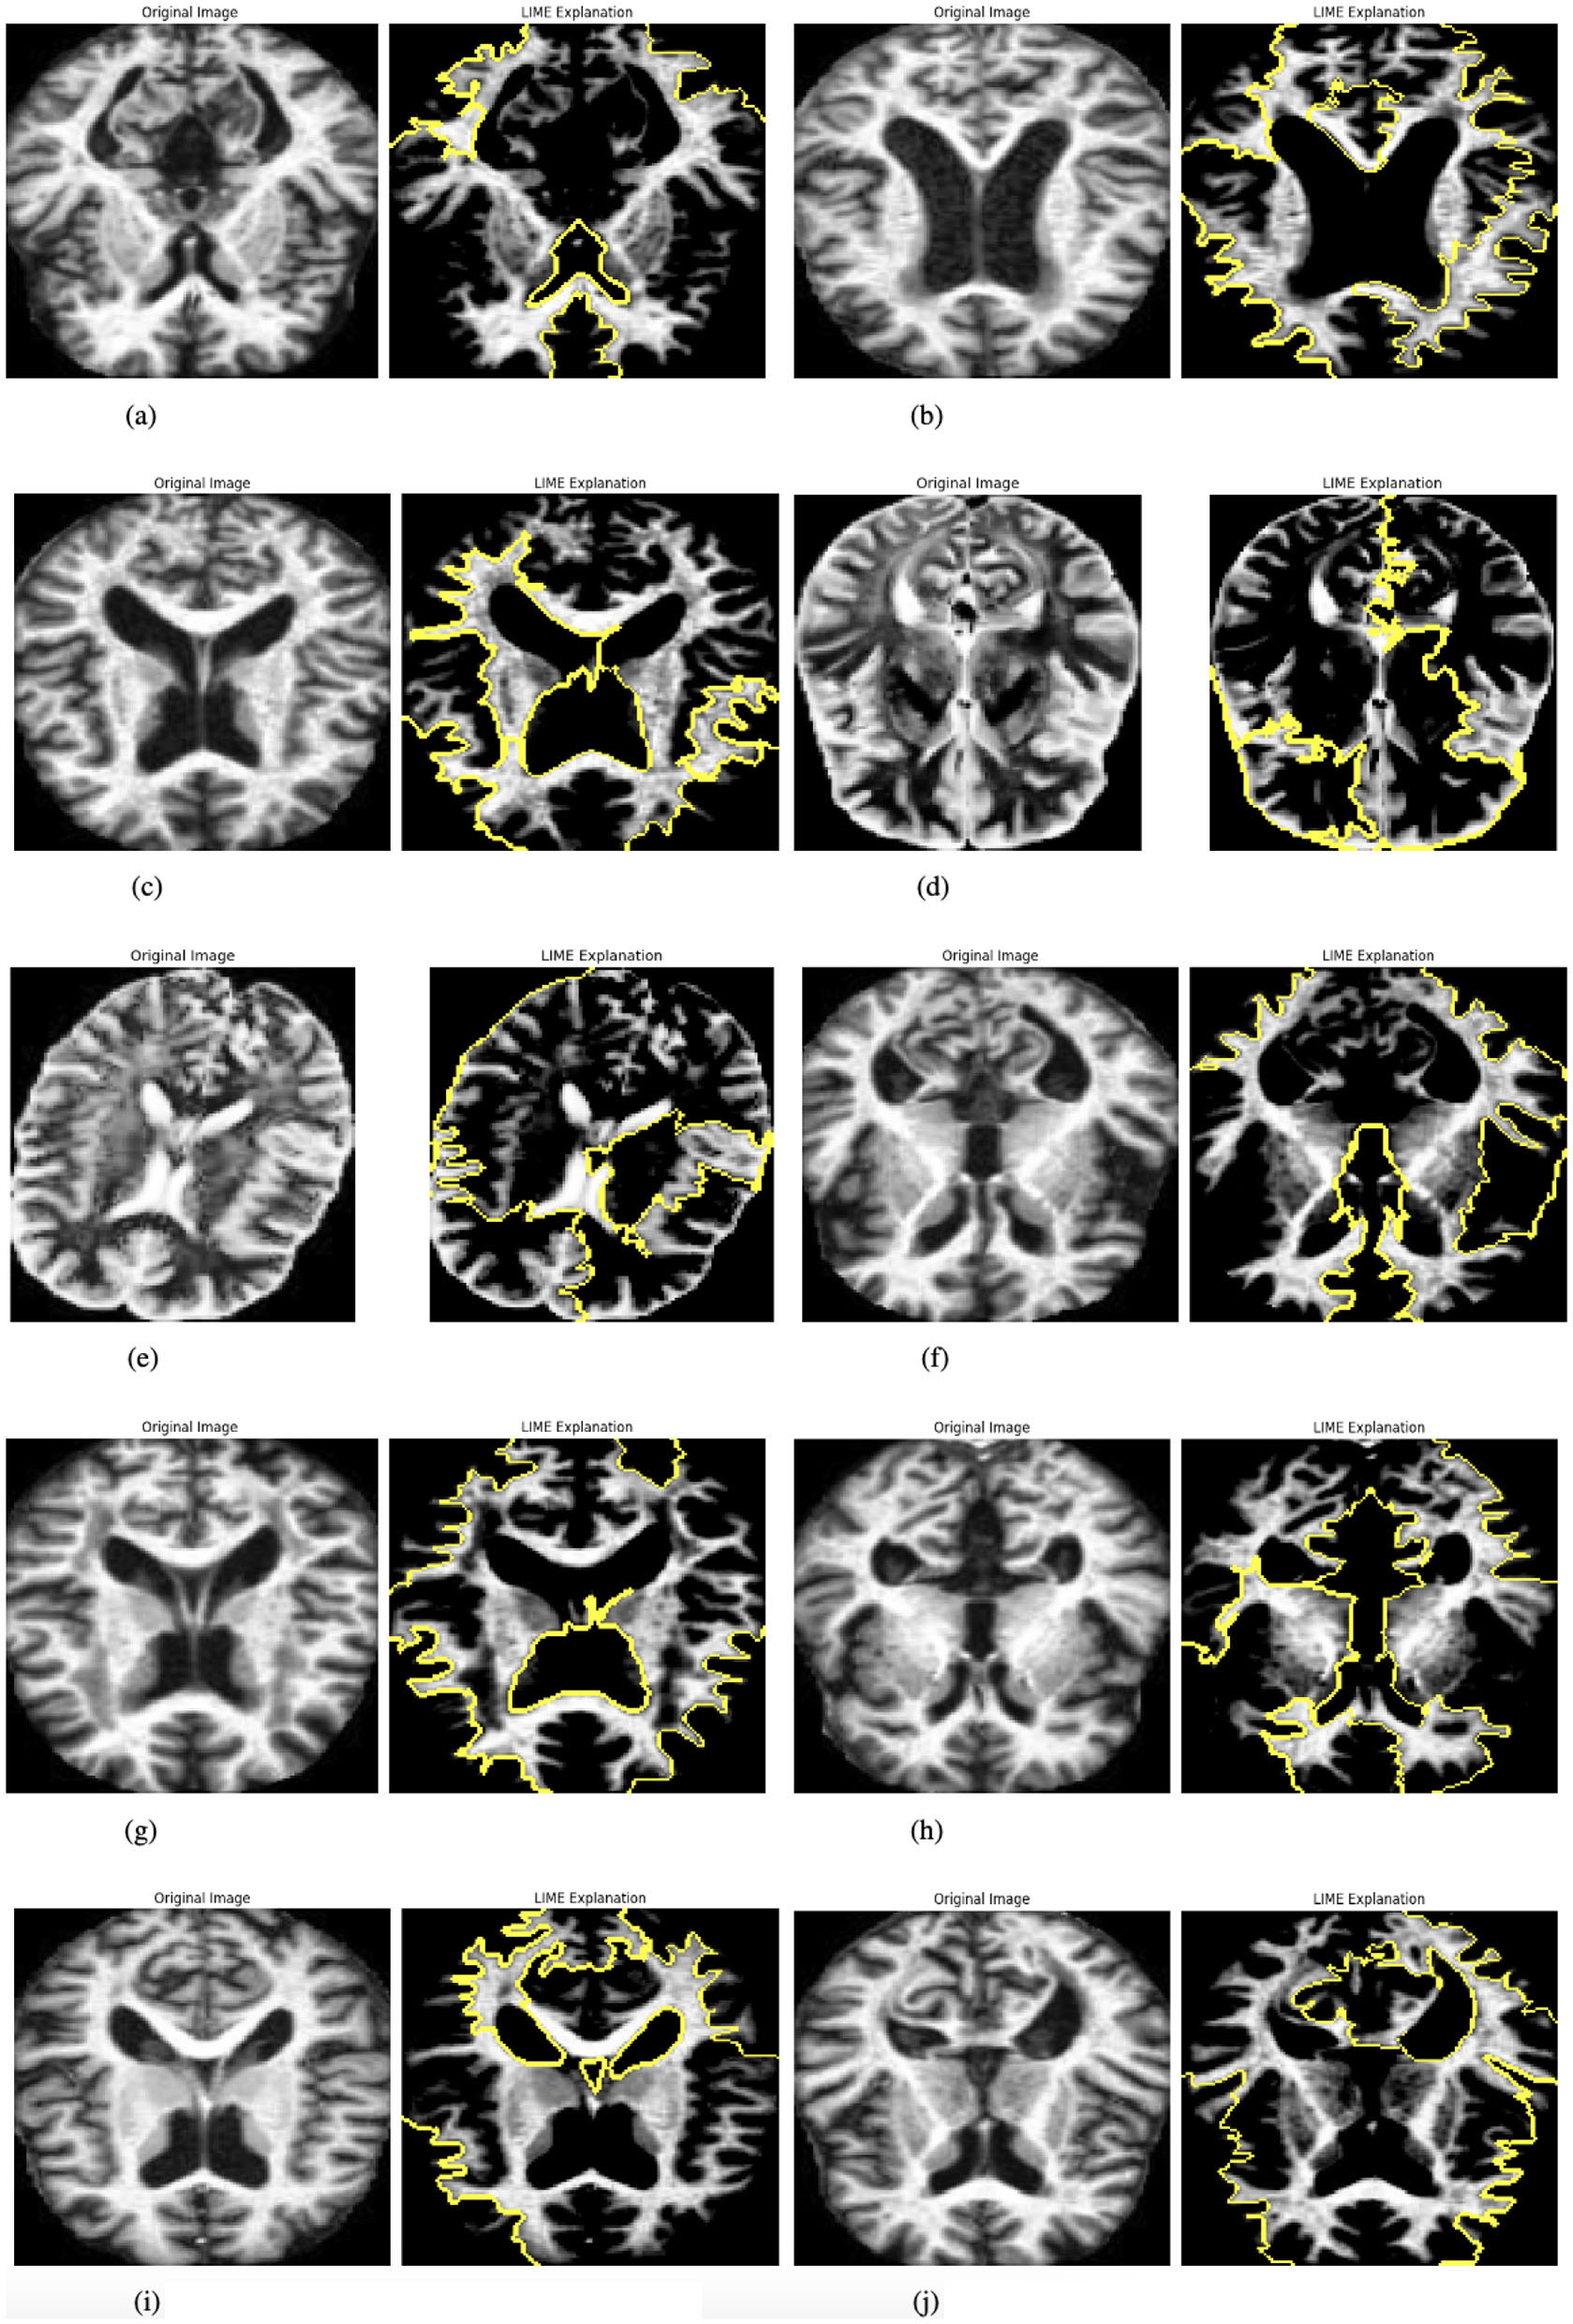

The model incorporates explainability through the use of LIME (Local Interpretable Model-agnostic Explanations) (27) to elucidate its predictions. A custom function, explain_model_predictions, is designed to integrate LIME into the workflow. The process begins with a preprocessing step where each input image is cropped to focus on the region containing the object of interest, achieved using a custom crop_to_object function. Since LIME requires three-channel images, grayscale inputs are converted to RGB format during preprocessing. Once prepared, LIME is applied to generate feature-based explanations for the model's predictions. This involves identifying and highlighting specific parts of the image that influence the model's output. To make these explanations accessible and intuitive, the original cropped image and its LIME-generated explanation are displayed side by side, facilitating easy comparison. This functionality is showcased for up to 10 images selected from the batch loader, providing a detailed explanation of how the model makes decisions. Figure 4 presented the selected images.

Figure 4

Graphical visualization of original image and explainability LIME of RbACNN model. (a) Original image and LIME explanation 1. (b) Original image and LIME explanation 2. (c) Original image and LIME explanation 3. (d) Original image and LIME explanation 4. (e) Original image and LIME explanation 5. (f) Original image and LIME explanation 6. (g) Original image and LIME explanation 7. (h) Original image and LIME explanation 8. (i) Original image and LIME explanation 9. (j) Original image and LIME explanation 10.